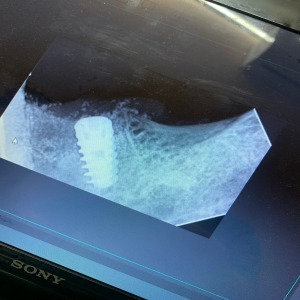

Dr. Anoop Dixit.

This clinic is running by Dr. Neelima Pandey Dixit & Team under the guidance of Dr. Anoop Dixit.

The clinic is equipped with all modern facility.